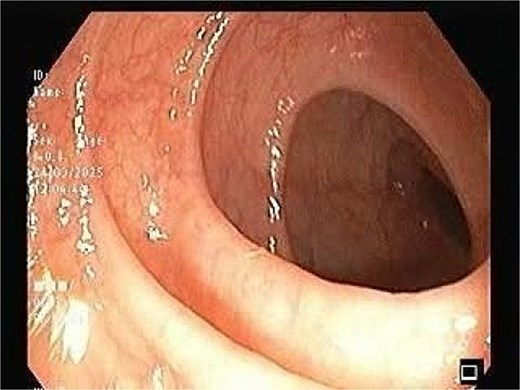

CT scan of the pelvis suggested a chronic inflammatory process. An MRI Perianal Region/Fistulogram (Fig. 1) was done and the findings were as follows: A possible fistulous tract was observed in the right perianal region, with a distal blind end in the intergluteal cleft. The presence of a fistulous tract and its extent was unclear. MRI findings could not differentiate between infectious, inflammatory, or neoplastic processes but it can definitely point out the presence of an abscess, which was not the case in our patient. Owing to the difficulty in establishing the diagnosis a colonoscopy was done and the findings (Figs 2 and 3) were as follows: A semicircumferential area from 7 to 11 o’clock position with tiny erosions was noted, which extended 4 cm from the anal verge.

The image depicting normal colonic mucosa up to caecum with normal vascular pattern.

No ulcerations, strictures, or masses suggestive of malignancy were detected. Endoscopic biopsies from the area suggested no specific pathology. The colonic mucosa appeared normal beyond the affected area, making systemic inflammatory disease less likely.